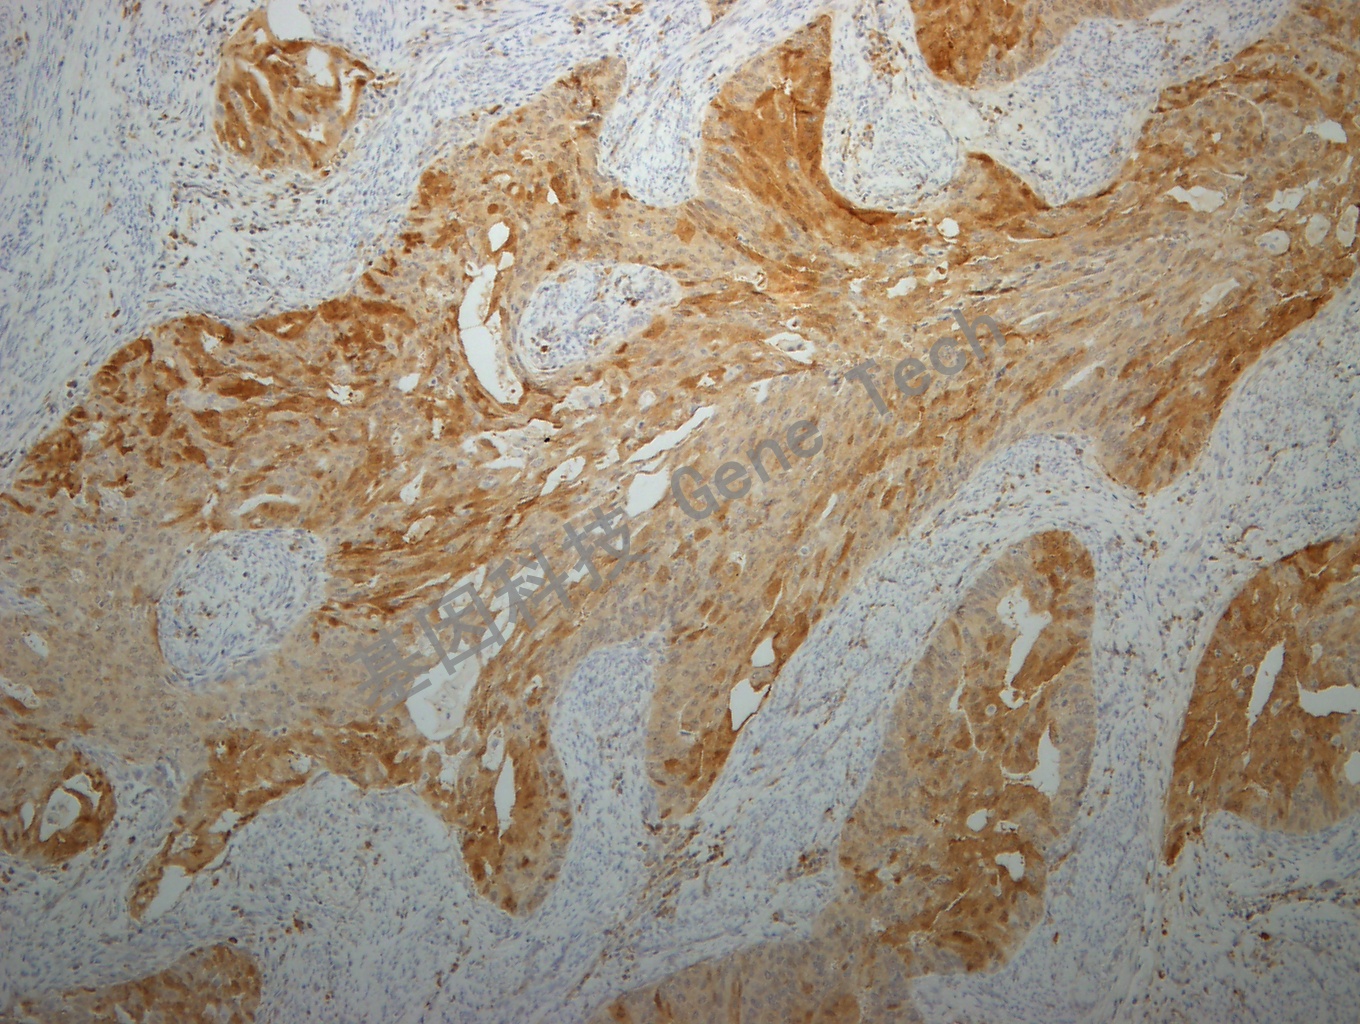

子宫内膜癌石蜡切片,用 p16(GT2013)染色,细胞浆/细胞核阳性,DAB显色。